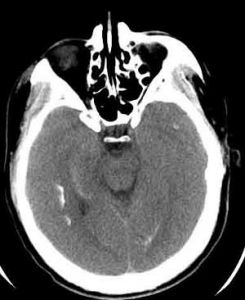

X線頭顱攝片多數可見基底神經節鈣化,骨質較密,小腦出現鈣化點。